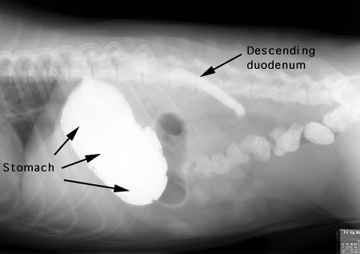

Barium was administered orally and the radiographs were taken 5 minutes later